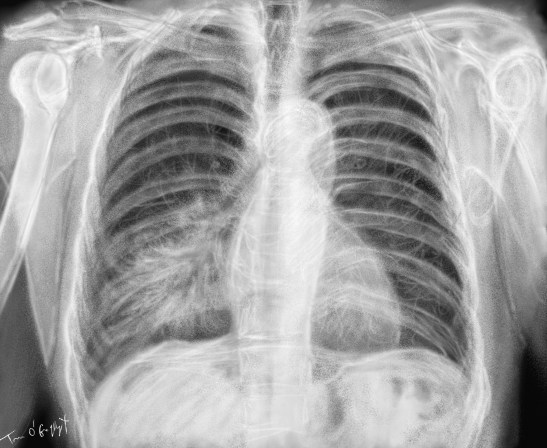

pneumonie infectieuse pneumopathie franche lobaire aigue

pneumonie lobaire inférieure droite à la radiographie de thorax

Publié le 2 décembre 2015 à 1755 × 1440 dans Pneumonies et pneumopathies infectieuses de l’adulte